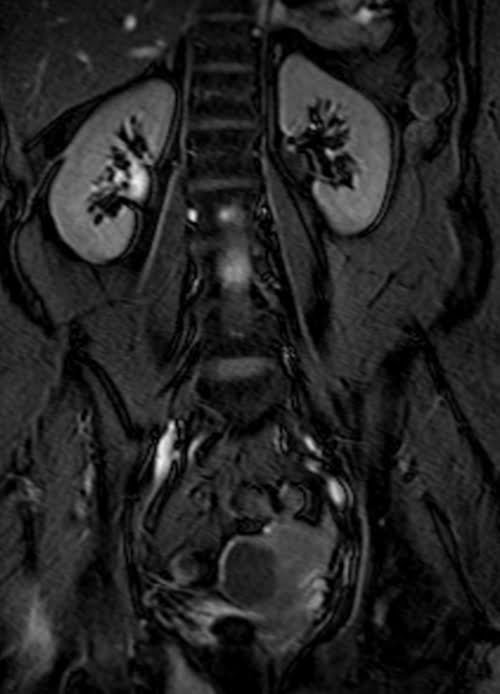

MRI kidney ureters and bladder( KUB) T2 TrueFISP fat saturated coronal images